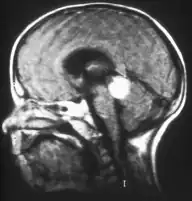

Trilaterales Retinoblastom

Trilaterales Retinoblastom nennt man ein sehr selten vorkommendes erbliches Retinoblastom, das gemeinsam mit einem Hirntumor auftritt. Dabei handelt es sich um eine selbständige Geschwulst, nicht um eine Metastase. Die Histologie ähnelt der des Retinoblastoms; die Prognose ist für den Patienten relativ ungünstig.

Gängige Untersuchungsmethoden sind insbesondere die Augenspiegelung (Ophthalmoskopie) und die Sonographie. In bestimmten Fällen wird zudem eine Computertomographie oder Magnetresonanztomographie vorgenommen, bei fortgeschrittenem Stadium der Krankheit auch eine Untersuchung von Liquor und Knochenmark, um eine Metastasierung feststellen zu können. Abzugrenzen ist die Retinale Dysplasie.